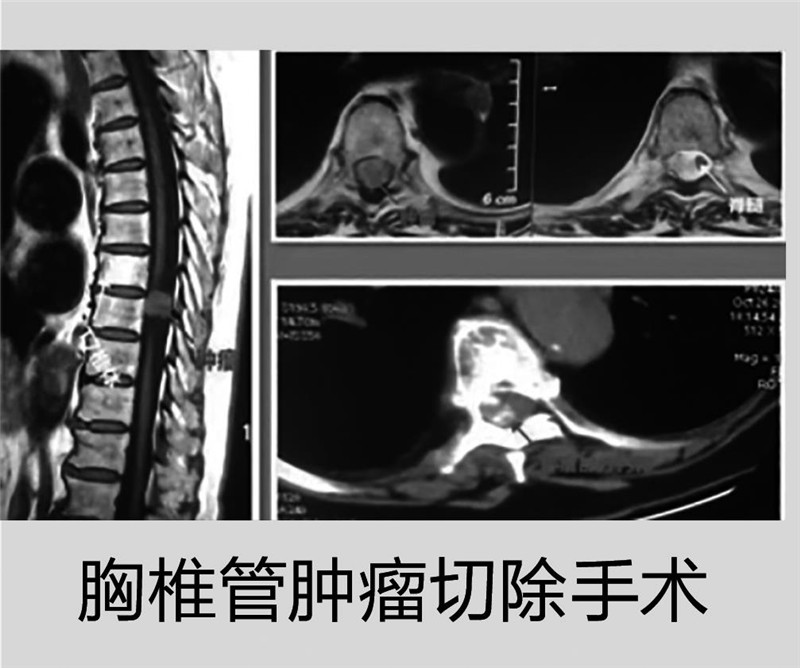

近期,该院外科接诊的一例巨大椎管内肿瘤的高龄患者:有高血压、高血糖、帕金森综合征多年,两年前检查就发现了胸椎管内巨大肿瘤,但因有一个腰椎椎体感染病灶,给予抗炎治疗近半年使椎管瘤手术被延误。手术前磁共振发现患者中胸段肿瘤已完全填满窄小的胸椎管,脊髓被挤压难以分辨,经多学科会诊后,张龙主任团队顺利为患者实施了胸椎管肿瘤的全切手术。手术后第二天,85岁的老人在卧床近两年后重新下地站立、双下肢肌力逐渐明显恢复。手术后第3天,患者可在简单搀扶下稳步行走。